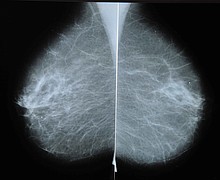

Mammograms pick up swelling due to Covid-19 vaccine, causing unnecessary fear, radiologists say

When she found a lump in her left breast during a routine self-check, Boston primary care physician Dr. Devon Quasha knew exactly what to do. She immediately scheduled a diagnostic mammogram and ultrasound at Massachusetts General Hospital for early January.